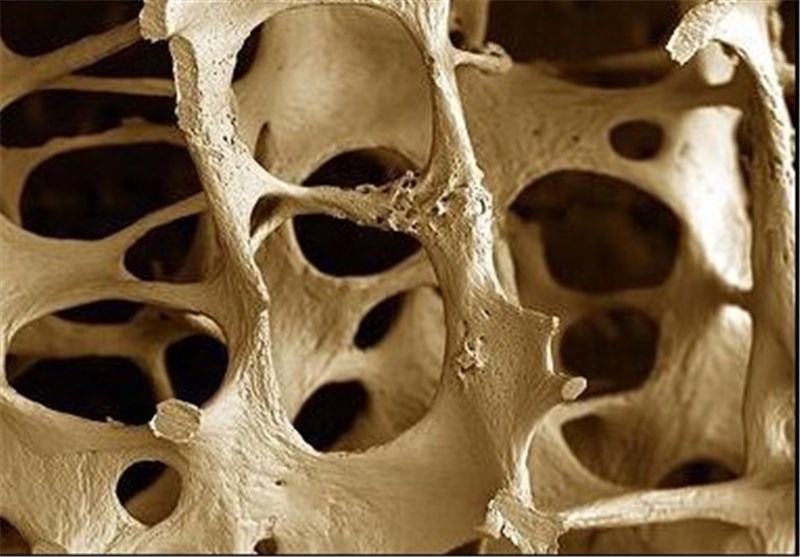

جهان صنعت نیوز، هر گاه تراکم و حجم مواد معدنی موجود در استخوانها از حد طبیعی کمتر شود، عارضه استئوپنی شکل میگیرد. تفاوت اصلی استئوپنی و استئوپروز در شدت کاهش تراکم استخوان است. استئوپنی، کاهش خفیف تراکم استخوان و مرحله پیشدرآمد پوکی استخوان است، اما استئوپروز (پوکی استخوان) یک بیماری جدیتر است که در آن تراکم استخوان به حدی کاهش مییابد که استخوانها در معرض شکستگی قرار میگیرند. شایع ترین و اصلی ترین علت بروز استئوپنی، افزایش سن است.